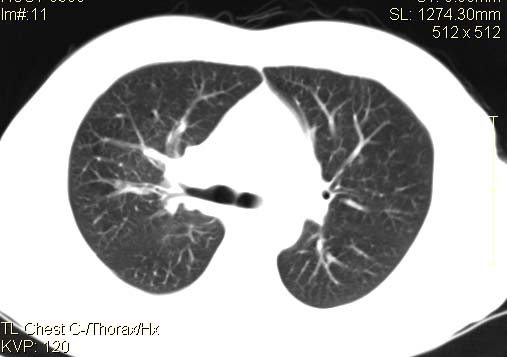

以下是引用qingyuan在2007-4-17 14:19:00的发言:[br]右肺下叶外侧后段胸膜下区节结样病变、分叶、内可见空洞,壁厚薄不均,胸膜凹陷、肺门周围区纹理增粗、僵硬、并近似小结节样改变,肺门区软组织节结、纵膈淋巴结肿大,患者病史长、抗炎治疗无好转炎性改变基本排除,考虑:右肺下叶周围型肺癌伴纵膈及右肺门区淋巴结转移、肺内淋巴管受侵。